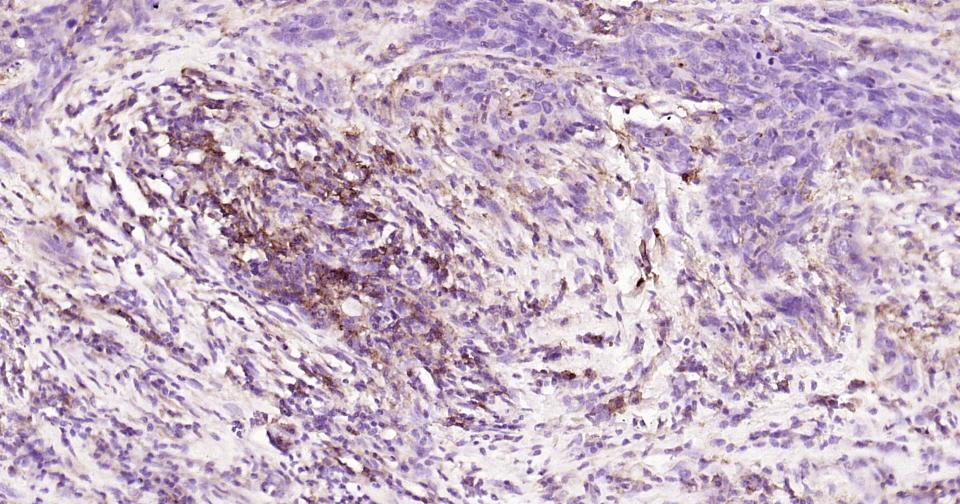

| IHC-P | Human | 1:100-500 | |